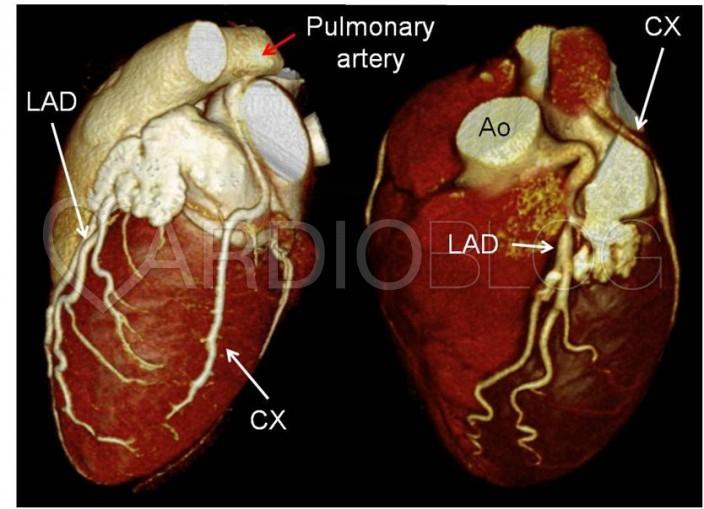

Az elvégzett coronaria CT angiographia tanulsága szerint a coronariák ectaticusak, kanyargós lefutásúak. A kanyarodó multiplanaris rekonstrukciókon jól ábrázolódik a jobb artéria pulmonalisból eredő körbefutó ág (CX). Az artéria pulmonalisban uralkodó nyomás jóval alacsonyabb a coronaria rendszer nyomásánál, így a kontrasztdús vér a CX-ből az arteria pulmonalis irányába áramlik, így a magasabb nyomású coronaria rendszer és az arteria pulmonalis között bal-jobb shunt alakul ki, mely „coronary steal phenomenon” kialakulásához vezet.